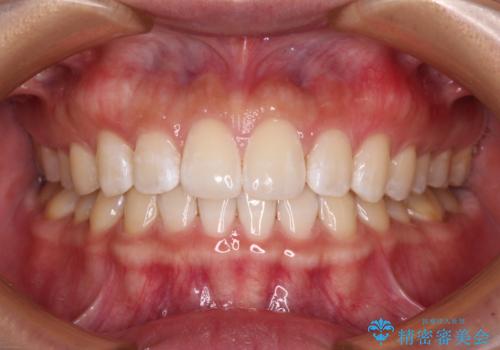

元々奥歯に負担のかかる咬み合わせですり減っていたため、仕上がった歯並びでも奥歯が咬んでいないように見えましたが、実際にはしっかりと咬合しており、患者様本人も咬んだ感触に違和感はないとのことでした。